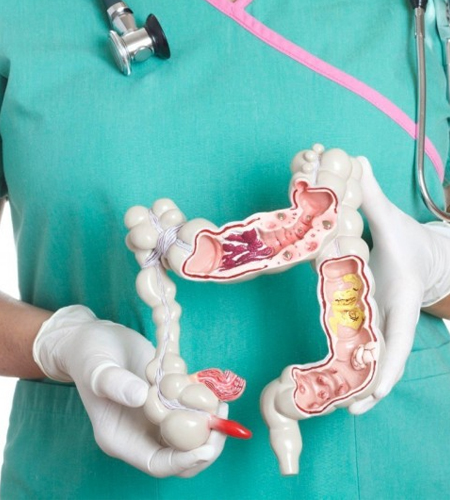

Tipos de exames

Toque Retal

O toque retal é um exame realizado para avaliar os problemas do reto e do ânus. Pode também auxiliar na avaliação ginecológica (problemas do canal vaginal e útero) [...].

Manometria Anorretal

O estudo manométrico da região anorretal tem por objetivo avaliar o tônus pressórico e a funcionalidade dos esfíncteres anais e a sensibilidade anorretal [...].